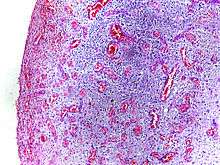

Morphologic patterns

Specific patterns of acute and chronic inflammation are seen during particular situations that arise in the body, such as when inflammation occurs on an epithelial surface, or pyogenic bacteria are involved.

- Granulomatous inflammation: Characterised by the formation of granulomas, they are the result of a limited but diverse number of diseases, which include among others tuberculosis, leprosy, sarcoidosis, and syphilis.

- Fibrinous inflammation: Inflammation resulting in a large increase in vascular permeability allows fibrin to pass through the blood vessels. If an appropriate procoagulative stimulus is present, such as cancer cells,[6] a fibrinous exudate is deposited. This is commonly seen in serous cavities, where the conversion of fibrinous exudate into a scar can occur between serous membranes, limiting their function. The deposit sometimes forms a pseudomembrane sheet. During inflammation of the intestine (Pseudomembranous colitis), pseudomembranous tubes can be formed.

- Purulent inflammation: Inflammation resulting in large amount of pus, which consists of neutrophils, dead cells, and fluid. Infection by pyogenic bacteria such as staphylococci is characteristic of this kind of inflammation. Large, localised collections of pus enclosed by surrounding tissues are called abscesses.

- Serous inflammation: Characterised by the copious effusion of non-viscous serous fluid, commonly produced by mesothelial cells of serous membranes, but may be derived from blood plasma. Skin blisters exemplify this pattern of inflammation.

- Ulcerative inflammation: Inflammation occurring near an epithelium can result in the necrotic loss of tissue from the surface, exposing lower layers. The subsequent excavation in the epithelium is known as an ulcer.